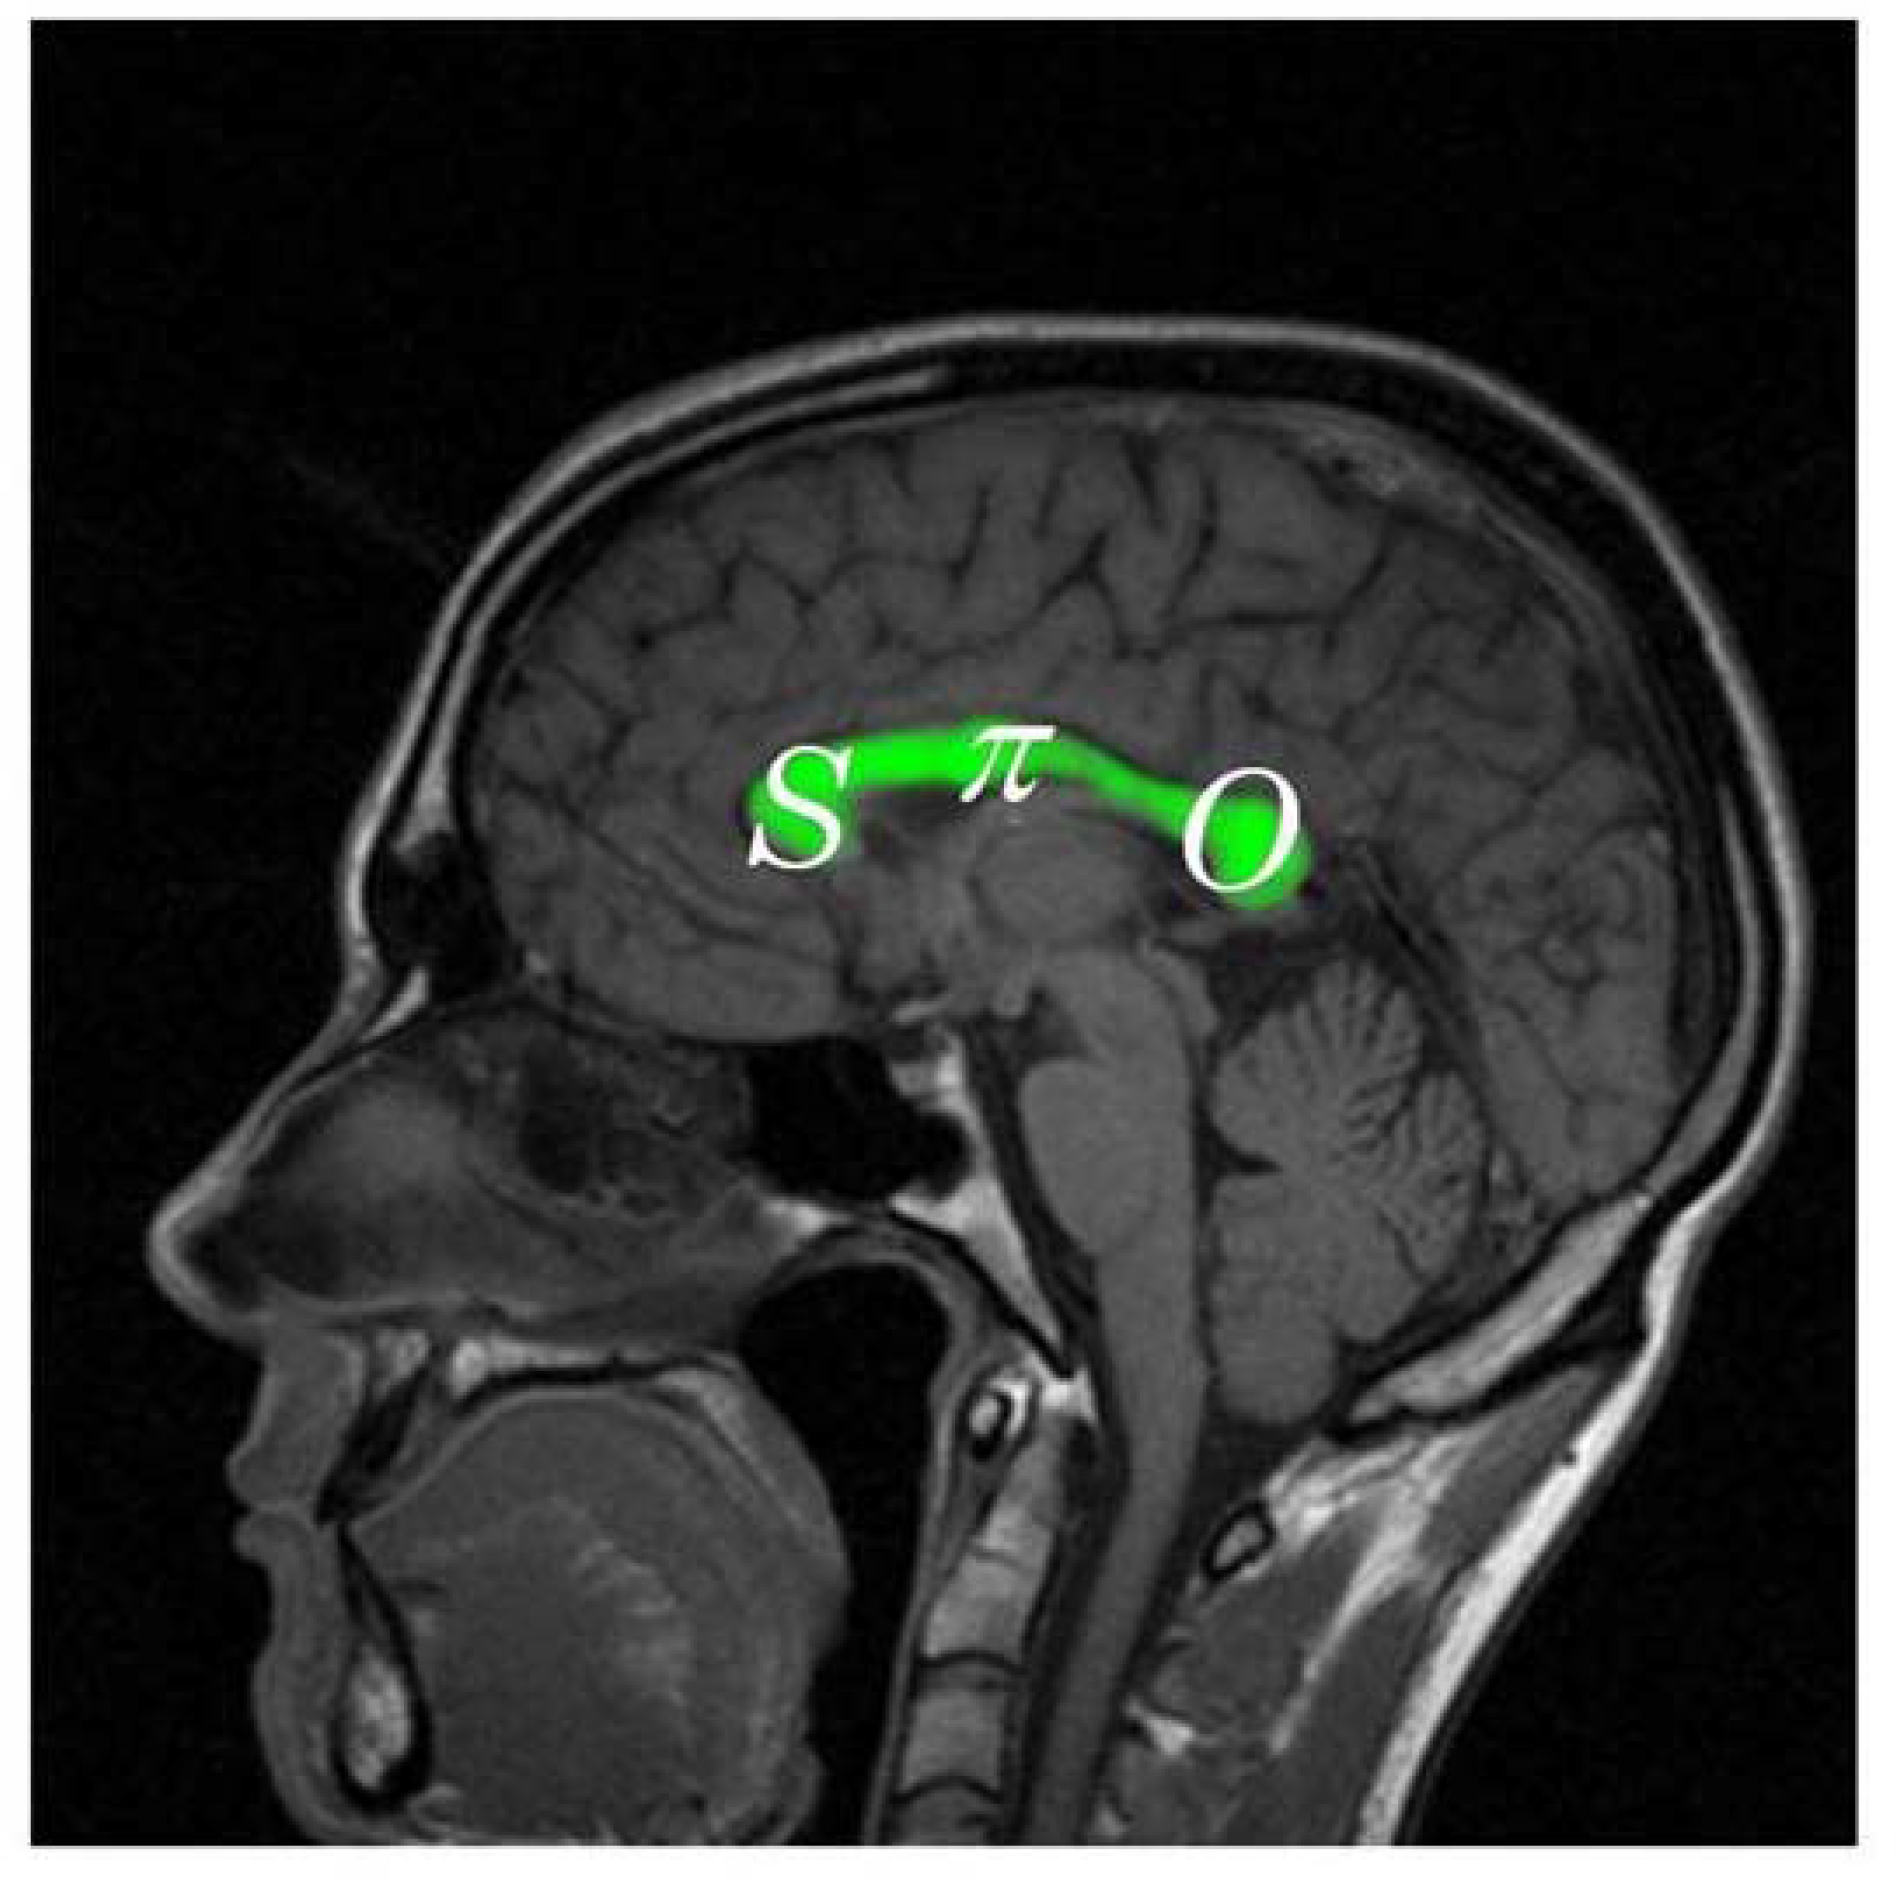

Furthermore, we must suppose that the development of the normal mapping of neurons through the corpus callosum must also reflect the same basic SπO formula as suggested in Figure 5. More specifically we must predict that the rostrum and genu (the bend) at the front of the corpus callosum should be associated with symbolic functions, S; the body of the corpus callosum should be associated with articulate and tactically complex motor sequences (as seen in speaking, writing, typing, and signing), π; and the basic sensory functions involved in constructing icons of objects should be associated with the posterior portion of the corpus callosum, O.

Figure 5.

The pragmatic mapping relation (in white lettering) hypothesized in the neuroarchitecture of the corus callosum (colored in green).

Until recently, with the development of diffusion tensor magnetic resonance imaging (dMRI)—e.g., see Paul, et al. [57] as well as Hofer and Frahm [58]—the inferences of Figure 5 could only be tested against symptomatic observations of persons with focal lesions in the corpus callosum. However, with dMRI it has become possible to map the estimated 190 million axons extending from the neuronal bodies extending from various regions of the cortex through the corpus callosum to the highest level of the neurons of the opposite hemisphere of the cortex as shown in Figure 6. The mapping actually found is indeed consistent with the formula, SπO. Also, as we should expect, focal lesions in the corpus callosum produce symptoms consistent not only with inferences at the global level of neuroarchitecture suggested in Figure 3, but also with considerably more specific predictions flowing from the hypothesized architecture of the corpus callosum suggested in Figure 5 and borne out in Figure 6.